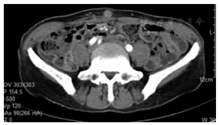

5例均在术前行腹部增强CT和MR排除腹腔及远处转移后行手术切除,术后恢复良好,无切口感染和切口疝发生。腹腔镜胃癌根治术大多采用"五孔法",各个穿刺孔都有可能发生种植转移。肿瘤位于皮下组织2例、肌层1例、脐部穿刺孔处2例(图1,图2,图3)。